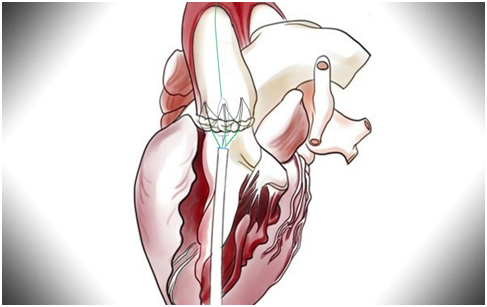

心脏中心成功为96岁高龄老人完成经心尖主动脉瓣置换术

1924年出生的李爷爷(化名)是我国著名的地质学家,退休后也一直在为我国的地球化学事业作贡献。仅在两年前,年近百岁的李爷爷身子骨还很硬朗,耳聪目明。但这两年的健康状况却急转直下,夜里睡觉总是间断地喘憋,白...